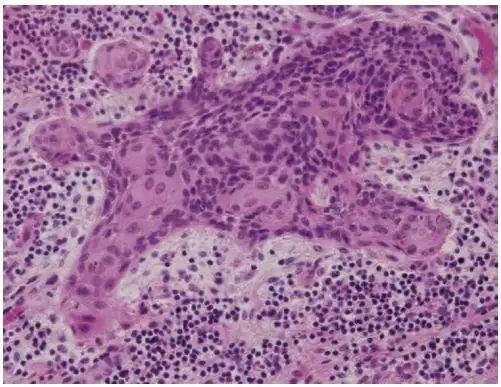

这个看上去像小狗的图像其实并不可爱,它是外阴浸润性鳞癌的病理图像[5]。出自纽约表维医院(Bellevue Hospital)的两位病理医生Khush Mittal和 Deline Da Costa之手。

这张病理图片中至少有3个浸润灶,究竟分布在哪里,欢迎火眼金睛的病理医生们献上答案呀!

外阴鳞癌约占外阴癌症的90%(其他的癌症类型包括黑色素瘤、肉瘤、基底细胞癌等),多发于老年女性,而且还有一部分外阴鳞癌与人乳头瘤病毒(HPV)感染有关[6]。

手术是早期外阴鳞癌的主要治疗手段,然而由于有些老年人不愿意或者不方便到医院看病,失去了早期诊疗的机会。所以,如果家里有老人身体不适,请及时就医诊治,一拖再拖病不会自然好了,反而会加重病情。